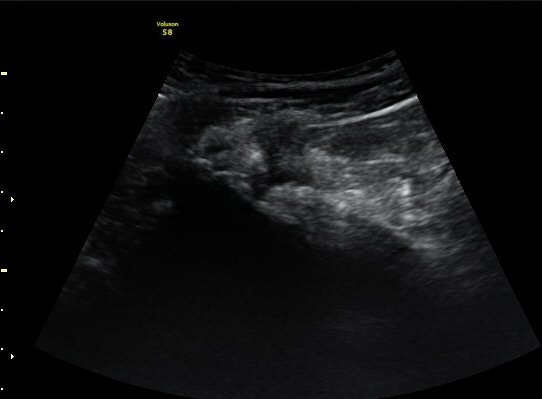

ŽÃËÀÚ¸¦ ¾ûµ¢ÀÌ °üÀý ¿ÜÃø Á¾´Ü¸é°Ë»ç ½Ã ÀüÇÏÀ屨(AIIS)¿¡¼­ ¼®È¸È­¼º À½¿µÀÌ °üÂûµÊ(»çÁø 2, 3).

¼±»óŽÃÊÀÚ¸¦ ÀÌ¿ëÇÑ °Ë»ç¿¡¼­ ÀüÇÏÀ屨ÀÇ ´ëÅðÁ÷±Ù ±â½ÃºÎ¿¡ ¼®È¸È­ À½¿µÀÌ ¶Ñ·ÈÈ÷

°üÂûµÊ(»çÁø 4, 5).